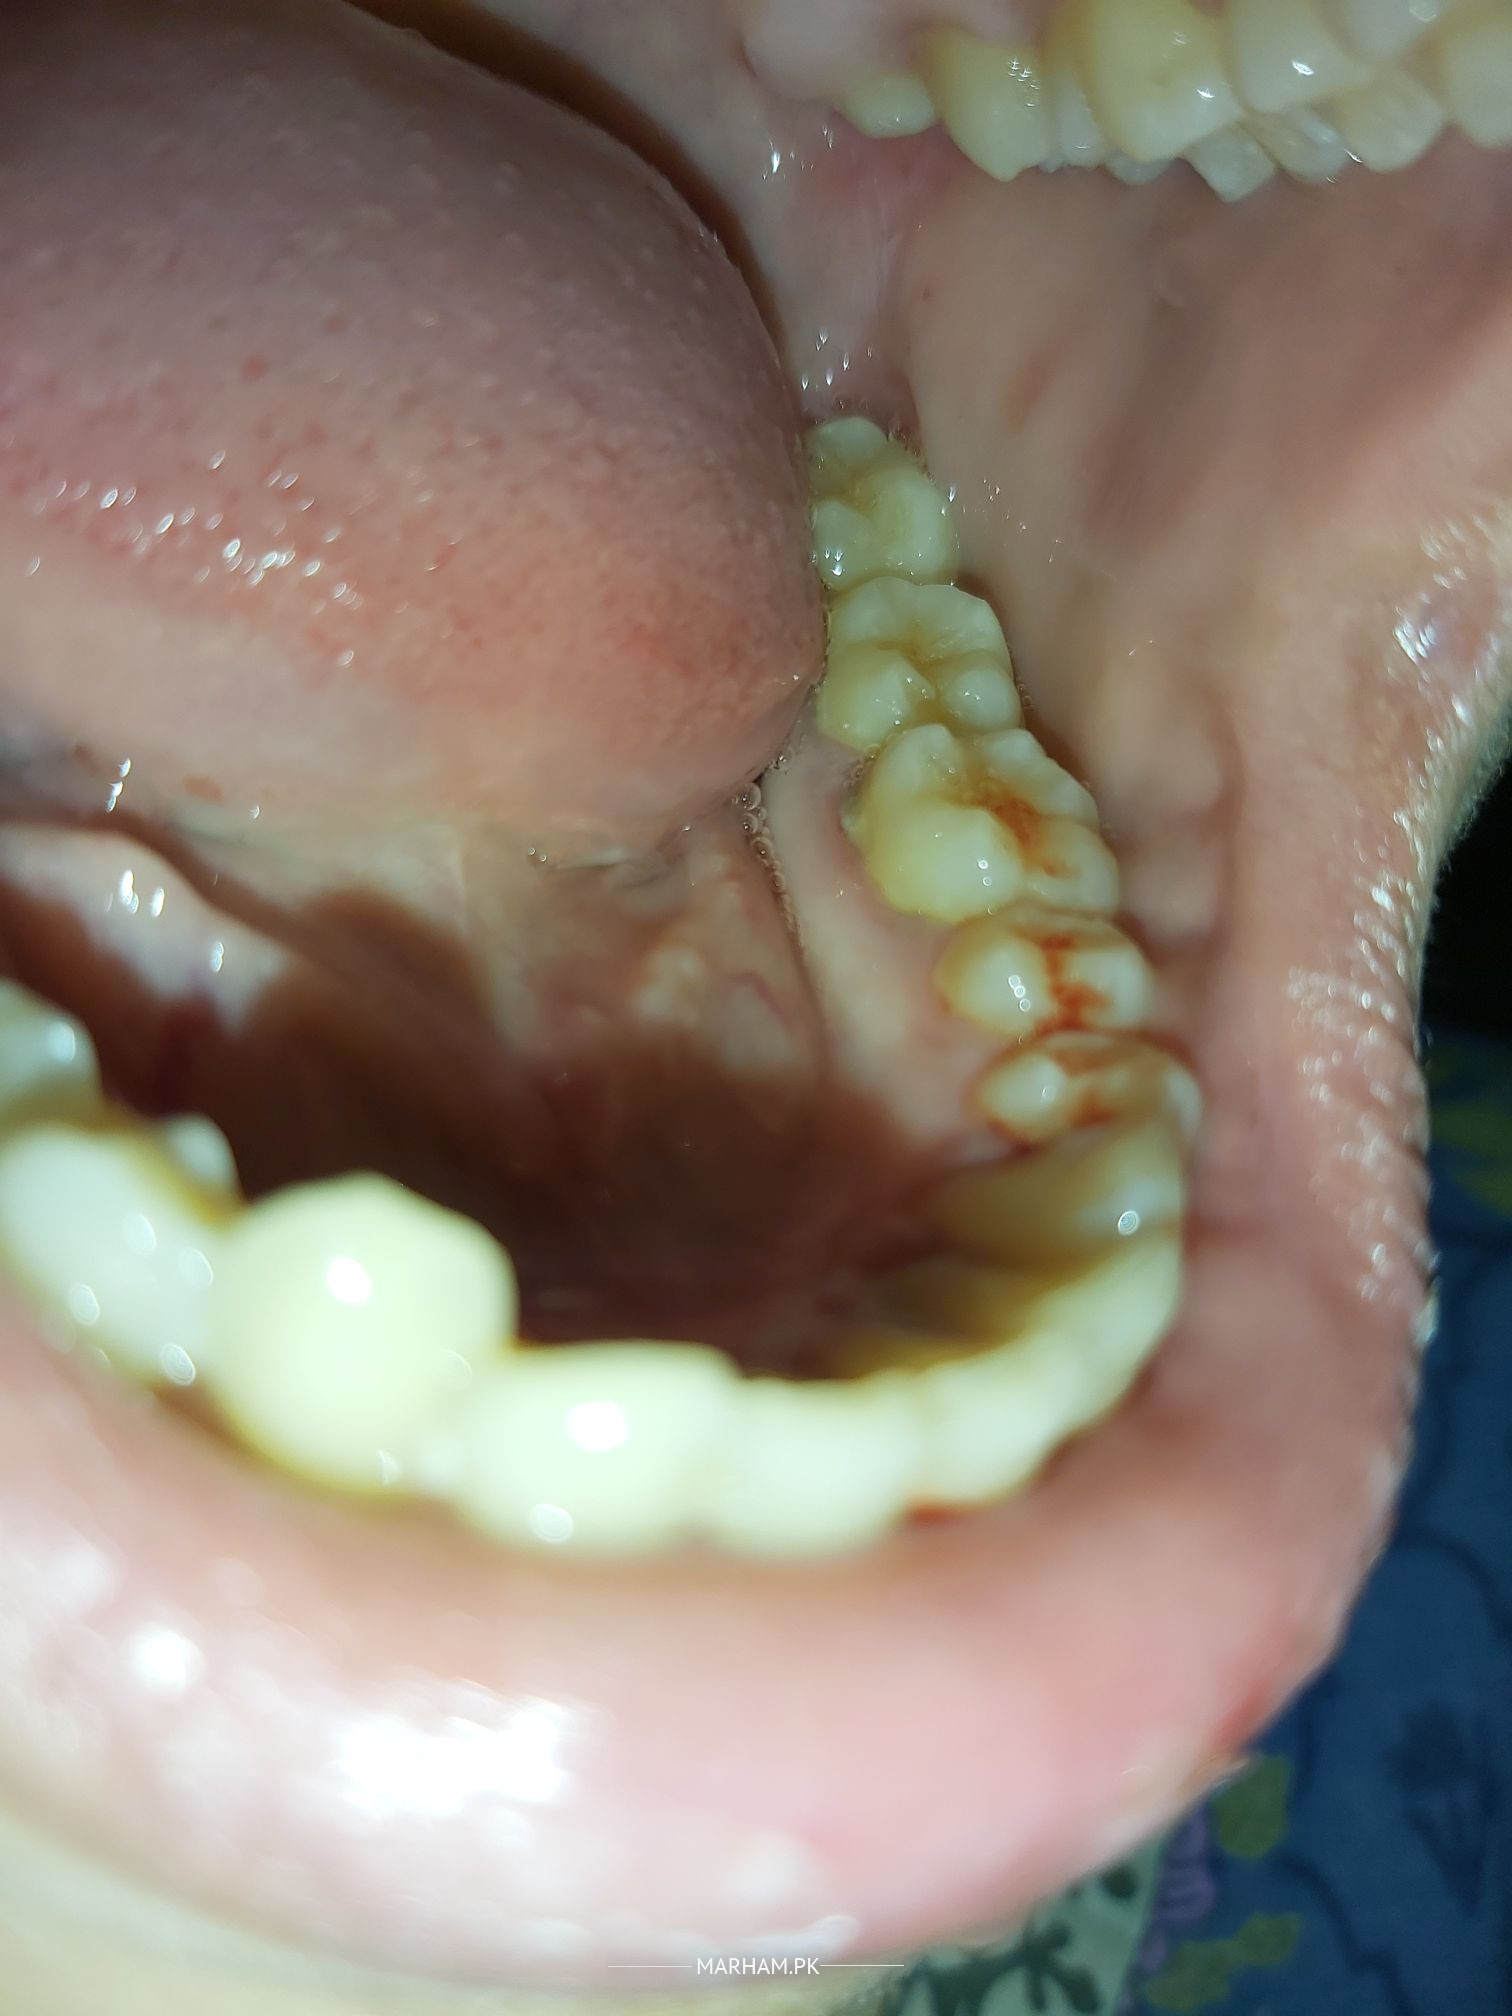

Hello reader !! from past months I am having gum bleeding, but sometimes it is in excessive amount. I have started taking vitamin C , my gums were fine but yesterday again I have conquered this issue. Bleeding is more when I pressed gum. Google is showing some super weird stuffs about this problem. Can you tell me what's the issue.

as per the image. it seems Gums infection.plz visit a dentist and get teeth cleaning and polish done.

You have gingivitis and need sub gingival (Deep) scaling

you need deep gums cleaning (scaling) your problem will b solved dont worry

Please visit my clinic. You are suffering from gingivitis

your gums are injected and require scaling for their treatment.